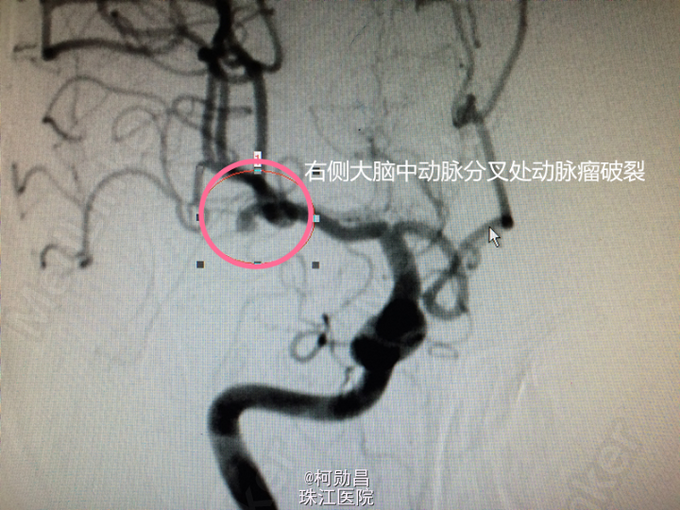

诊断:蛛网膜下腔出血破入脑室:动脉瘤? 处理:急诊予全脑血管造影提示:右侧大脑中动脉分叉处动脉瘤,予介入栓塞治疗(弹簧圈),并予去骨瓣减压术治疗。

颅内动脉瘤是蛛网膜下腔出血(SAH)的首要病因,而大多数的动脉瘤是在破裂后才发现的。90%动脉瘤好发于Willis环上,大脑中动脉动脉瘤发病占20%左右。动脉瘤破裂者,3天之内可及时行全脑血管造影术并行介入栓塞治疗;出血3天之后到出血水肿期,则禁止行介入治疗,先行保守治疗或手术治疗,约1周后度过水肿期再行栓塞治疗。这个病例诊治及时,预后良好。